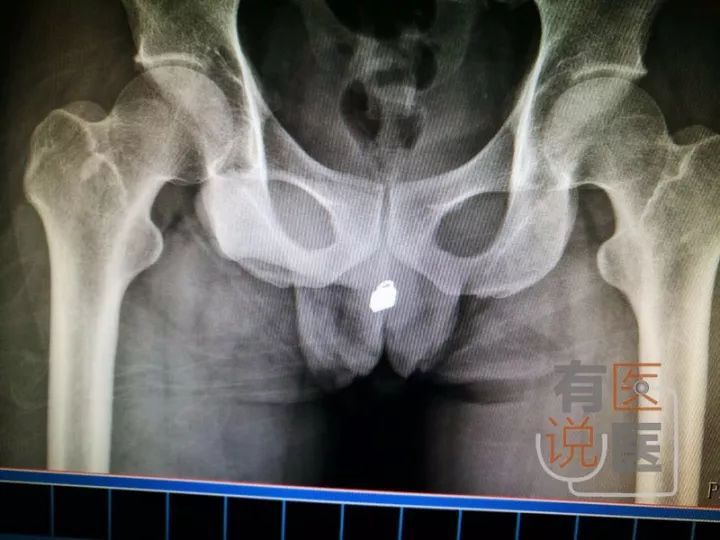

前阵子,福州某收治了一名31岁特殊的男性患者。